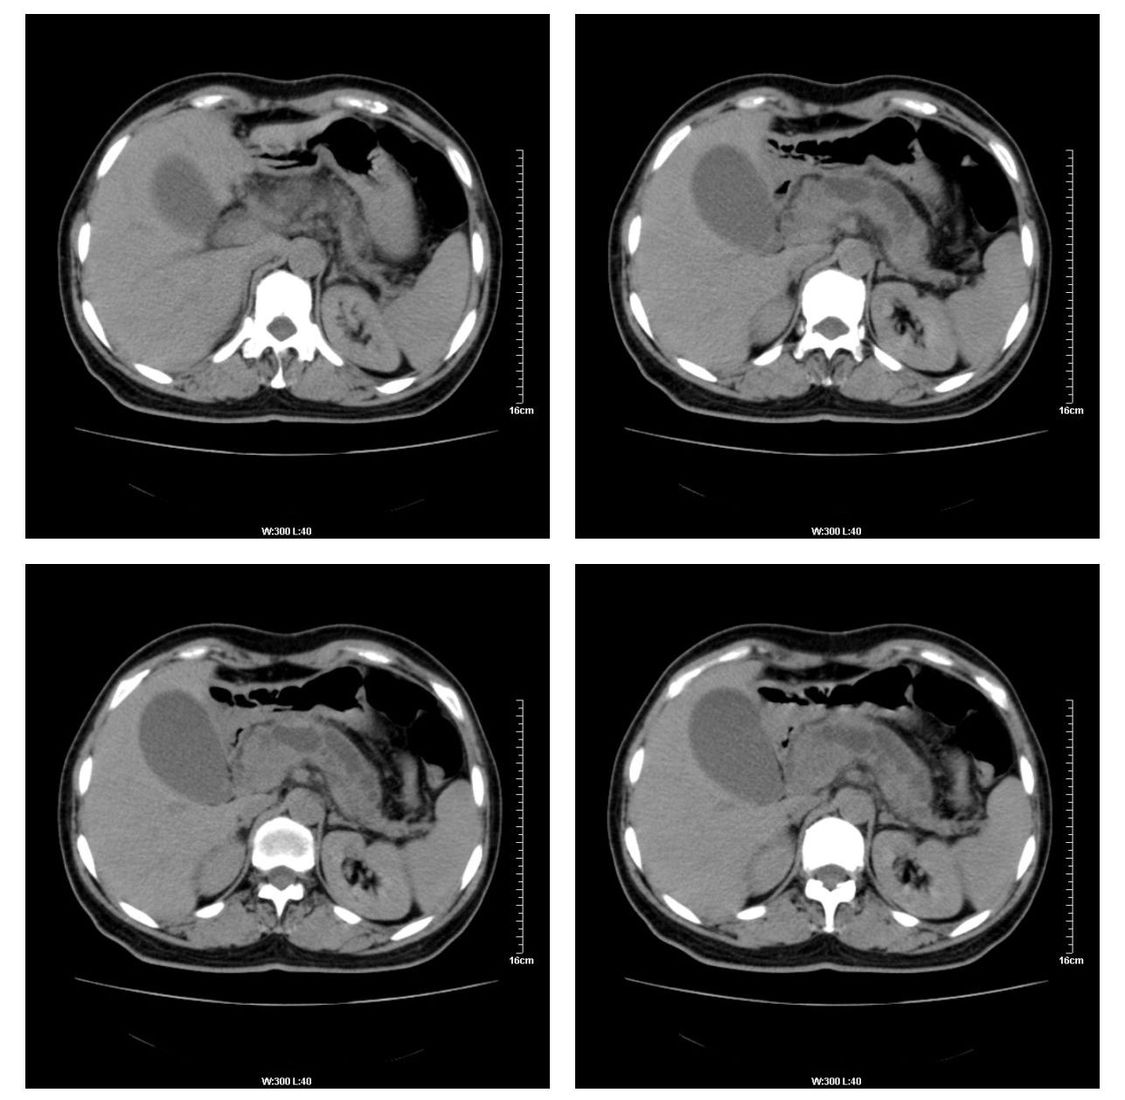

标题: CT13800:女性,52岁。腹痛、腹胀、消瘦及乏力5个月。 [打印本页]

标题: CT13800:女性,52岁。腹痛、腹胀、消瘦及乏力5个月。

慢性胰腺炎、胰腺假囊肿形成,胆总管梗阻,胆囊扩张

慢性胰腺炎、胰腺假囊肿形成。

慢性胰腺炎、胰腺假囊肿形成,胆总管梗阻,胆囊扩张,不除外胰腺占位

考虑慢性胰腺炎、胰腺假囊肿形成。

各期时间抓的不太好,门静脉始终显示不佳(门脉瘤栓形成?)。